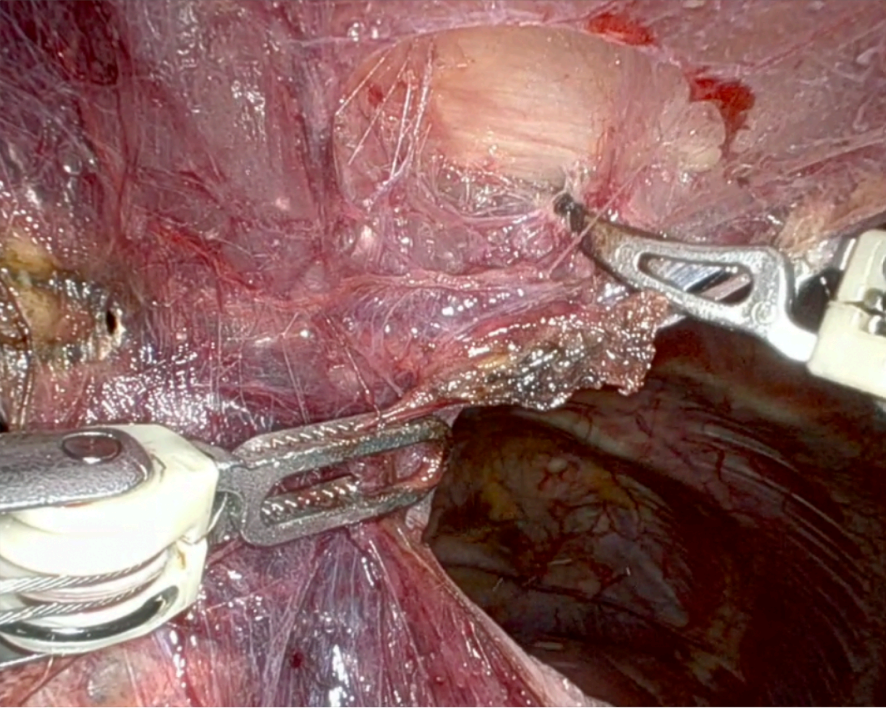

2A: Substernal Dissection

The procedure started by dividing the tissue beneath the sternum from the lower to the upper edge of the manubrium. This maneuver, combined with CO2 inflation, created a large operative space with anatomical landmarks that could be easily identified: the left and right internal arteries and the left and right phrenic nerves. The surgeons continued by dividing the lower thymic horns. Using the Syncrosyl, the surgeons safely divided large arteries and veins that supplied blood to the mediastinal fat tissue. Dissection was continued, separating the fat tissue from the pericardium plane in an upward direction, exposing the ascending aorta and the superior cava vein.